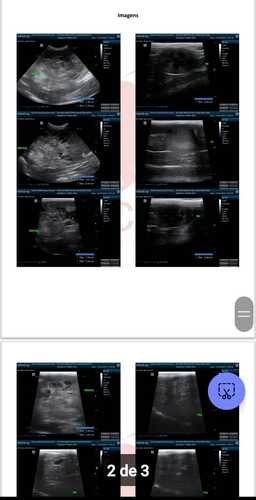

O Plutão está comigo e com a minha família há 10 anos. Ele apareceu na nossa vida logo depois que minha mãe faleceu e, desde então, virou parte da casa, trazendo alegria pra todo mundo. Mas, infelizmente, agora ele precisa da nossa ajuda. Descobrimos que o Plutão tem um tumor grande no fígado. No começo, achamos que não tinha mais jeito... Mas ele mostrou que ainda tem muita vontade de viver! Trouxemos ele pra casa e, nos últimos 20 dias, ele melhorou bastante. Isso nos deu esperança de buscar um tratamento. A boa notícia? Existe uma cirurgia que pode salvar a vida dele! A ruim? O custo é alto, e a gente já gastou tudo que podia com exames e internações. Por isso, estamos pedindo sua ajuda! Qualquer valor faz diferença e vai direto pra tomografia, cirurgia e internação dele. Se puder doar, saiba que estará dando ao Plutão a chance de continuar com a gente por mais alguns anos, cheio de vida e carinho. Se não puder doar, compartilhar já ajuda demais! Vamos juntos dar essa chance pra ele?